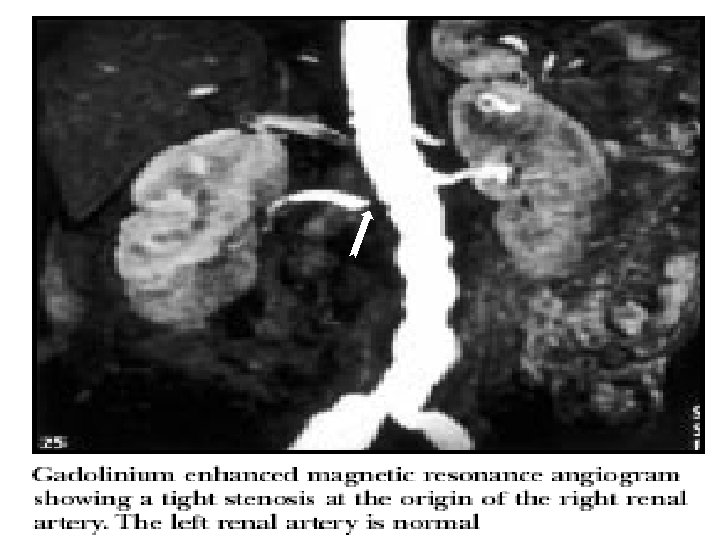

Инструментальные методы обследования § Рентгенологические -обзорная рентгенография (тени конкрементов) -экскреторная урография (визуализация почек, ЧЛС, мочевыводящих путей, оценка функции) -КТ, МРТ (опухоли, кисты) -ангиография (выявляет стеноз почечных артерий, опухоли, тромбоз почечных вен, нарушение функции) § Радионуклидные -оценка формы, размера и функции каждой почки - «каптоприловая проба» при подозрении на стеноз почечной артерии

Проходимость артерии восстановлена после стентирования